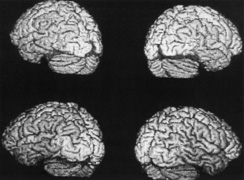

OPTIC TRACTS The optic tract is the continuation of the anterior visual system from the optic chiasm to the LGN. Only the contralateral hemifield is represented. The decussated nasal retinal fibers are not initially well aligned topographically with the other eye's temporal retinal fibers, but retinal correspondence improves towards the termination of the tract at the lateral geniculate nucleus (LGN). The retinotopic map is also tilted in the optic tracts, so that the macula is represented dorsally, inferior retina (superior visual field) laterally, and superior retina (inferior visual field) medially (see Chapter 4, Fig. 9).1 The magnocellular and parvocellular axons also may be segregated, with magnocellular axons more ventral.2 Both of these topographies are mirrored in the LGN. The main vascular supply of the optic tract is the anterior choroidal artery. The functional anatomy of the optic tract is reflected in several important clinical findings. First, partial lesions cause contralateral homonymous defects that can be markedly incongruous (different patterns of visual loss in the two eyes) because of the poor topographic alignment of the two retinal maps (Figs. 1 and 2).3,4 In contrast, lesions of the optic radiations cause only mild incongruity and striate lesions are highly congruous. Complete transection of the optic tract leads to congruous complete hemianopia, although this is less frequent than partial lesions. Reduced acuity with an optic tract lesion indicates bilateral tract damage or extension of the lesion to the optic chiasm or optic nerves.4,5 Second, because the axons in the optic tract originate from retinal ganglion cells, damage to the tract causes optic atrophy over time. This is present in both eyes, but because only half or less of the axons of each eye are affected, the atrophy is less severe than with most optic neuropathies. Also, the pattern of optic atrophy differs between the eyes. In the eye with temporal field loss, the axons from the nasal retina are affected. The fibers from the nasal periphery enter the nasal side of the disc, whereas those from the nasal macula enter the temporal disc in the papillomacular bundle. Atrophy is seen in these nasal and temporal wedges of the disc but the superior and inferior sectors are spared, because these contain fibers from the temporal retina. The result is “bow-tie” optic atrophy (see Fig. 1). In contrast, atrophy in the eye with nasal field loss affects the superior and inferior wedges and papillomacular bundle, but not the nasal wedge. This appears as diffuse or temporal disc pallor. Another distinctive optic disc picture occurs in the eye with temporal field loss when a mass lesion causes papilledema and compresses the optic tract. Disc swelling occurs in the superior and temporal disc but not in the atrophic bow-tie regions, creating “twin-peaks” papilledema (see Fig. 2).6,7 Third, because fibers for the pupillary reflex also travel in the optic tract, often there is a relative afferent pupillary defect (RAPD). With a significantly incongruous hemianopia, the RAPD may be in the eye with greater visual loss. With a complete tract lesion the RAPD is in the eye with temporal field loss,4,8 because the temporal hemifield is larger and there are slightly more axons from the nasal than temporal retina (ratio 53:47). The RAPD is a useful sign in optic tract hemianopia because it may be present at a time when optic atrophy has not yet developed (see Chapter 15).9 Other reported pupillary abnormalities include Wernicke's hemianopic pupil, which is an intraocular afferent pupil defect, with less pupillary constriction from light on the hemianopic hemiretina compared to light on the intact hemiretina. Wernicke's hemianopic pupil is difficult to elicit at the bedside because of intraocular light scatter,3 although it may be seen with computerized pupillometry (Fig. 3). The combination of optic atrophy, RAPD and field incongruity is important to recognize with homonymous hemifield defects, because it changes the differential diagnosis of hemianopia (Fig. 14). Most hemifield defects from lesions of striate cortex or the optic radiations result from vascular disease or other intracerebral pathology. Most optic tract lesions are compressive extrinsic masses, with a differential diagnosis similar to that for optic chiasmal lesions (see Chapter 6). In fact, patients with combined damage to the optic tracts, chiasm, and nerve are not rare.4,10–13 Pituitary adenomas, giant aneurysms of the internal carotid artery, meningiomas, and craniopharyngiomas are the chief causes of optic tract dysfunction. The investigation of choice is imaging of the parasellar region, with coronal and axial sections and contrast administration. Less common lesions include inflammatory conditions such as multiple sclerosis3,11,14,15 and sarcoidosis (see Fig. 1).16 Intrinsic optic pathway gliomas may occur in the optic tracts. Vascular lesions are rare, but there are reports of cavernous angiomata10,17 or arteriovenous malformations.18 Optic tract infarction can complicate anterior temporal lobectomy, possibly from vasospasm of the anterior choroidal artery.19 Trauma can affect the optic tract.3 Radiotherapy of pituitary tumors may be followed years later by optic tract necrosis.13 Optic tract dysfunction is a side effect of alpha-interferon.20 On occasion there is congenital absence of the optic tract 21; such patients are often unaware of their hemianopia. Associated abnormalities are unusual.3 These include endocrine disturbances from hypothalamic dysfunction and memory impairment from temporal lobe involvement,22 reflecting the proximity of the optic tracts to these structures (see Chapter 4). LATERAL GENICULATE NUCLEUS The LGN is a subnucleus in the ventro-postero-lateral corner of the thalamus. Neighboring thalamic subnuclei include the medial geniculate nucleus ventromedially, ventral posterior nucleus dorsomedially, and pulvinar superiorly and dorsally. The medial geniculate nucleus gives rise to the acoustic radiations, which pass by the dorsomedial aspect of the LGN on their way to the auditory cortex in the temporal lobe. The optic radiations arise from the dorsolateral surface of the LGN. Ventrally, the hippocampus and parahippocampal gyrus face the LGN across the ambient cistern and the inferior horn of the lateral ventricle. The LGN has a dual blood supply: the anterior choroidal artery, a branch of the internal carotid artery, and the lateral choroidal artery, a branch of the posterior cerebral artery. The anatomy of the vascular territories within the LGN has been debated. Initial studies suggested that the anterior choroidal artery supplied the medial LGN as well as the optic tract and the lateral choroidal artery the lateral LGN. However, experience with surgical arterial lesions concluded that the anterior choroidal artery supplied both the lateral and medial aspects and the lateral choroidal artery supplied the hilus and midzone of the LGN. In addition to its function as a relay in the visual pathway, the LGN is also a site of modulation, by back-projections from visual cortex23,24 and afferent projections from the brainstem reticular formation and superior colliculus.25 Some of the corticofugal input influences the stimulus selectivity of LGN neurons.24 Others postulate that these nonretinal inputs play a role in gating visual transmission through the LGN, and thus participate in selective attention.23 The LGN is a triangular shaped structure with six roughly horizontal layers containing segregated inputs from the two eyes (see Chapter 4, Fig. 8). The ventral two layers are the magnocellular layers, whereas the other four layers are the parvocellular component; these differ in many structural and functional aspects (see Chapter 4). The LGN has a retinotopic pattern that is a continuation of that found in the optic tract. The macula is represented in a dorsal wedge, including the hilum and projecting posteriorly, whereas the most peripheral fibers are located ventrally. Superior retinal fibers (contralateral inferior visual quadrant) are in the medial horn and inferior retinal fibers (contralateral superior visual quadrant) are in the lateral horn. Because the LGN is small and relatively secluded, lesions here are rare. Its intimate relation to the optic tract and optic radiation make it difficult to be certain that a visual defect results from LGN damage rather than damage to these structures. Indeed, visual field defects from purported LGN lesions resemble visual field defects from optic tract or optic radiation lesions. Three main types of hemianopic defects have been described. The first is an incongruous hemianopia, much like that seen with optic tract lesions, reflecting the continued segregation of ocular inputs in the LGN. The other two patterns are sectorial hemianopias reflecting the unusual territorial division between the anterior and lateral choroidal arterial supplies. With lateral choroidal ischemia, the hilum and middle zone of the LGN are affected, causing a wedge-shaped visual defect straddling the horizontal meridian (Fig. 4).26 With anterior choroidal ischemia, the lateral and medial tips of the LGN are infarcted, resulting in the reverse defect, loss of the superior and inferior aspects of the contralateral hemifield with sparing around the horizontal meridian.27,28 Unusual cases of presumed bilateral LGN damage have presented with an “hourglass” shape to either the visual field defect29,30 or the region of spared vision.31 Optic atrophy often accompanies LGN lesions. If there is damage to almost all of the LGN, the optic atrophy has a similar appearance to that seen with optic tract lesions. If there is partial damage causing sectorial hemianopias, then the optic atrophy may be more subtle and restricted to the relevant sectors of the disc.26,27 However, because the afferent fibers subserving the pupillary light reflex already have departed for the pretectum, there is no RAPD with lesions of the LGN. With incongruous hemianopia and optic atrophy, this is the only feature that permits distinction between optic tract and LGN lesions. A variety of pathologies have been reported with LGN lesions. Infarction is the most likely cause of sectoranopia, given the dependence of such defects on the vascular anatomy,26,27 but astrocytomas and arteriovenous malformations are also reported. Furthermore, the LGN appears to be a target of central pontine myelinolysis, a syndrome associated with excessively rapid correction of hyponatremia.29,30,32 LGN damage rarely is a parainfectious complication of traveler's diarrhea.31 OPTIC RADIATIONS The optic radiation may be affected anywhere in its course (see Chapter 4); the type of visual field defect reflects the site of damage. Ischemic or hemorrhagic lesions of the internal capsule affect the optic radiation while it is still a relatively compact bundle, usually causing a complete homonymous hemianopia. A similar defect can arise from damage close to the termination in striate cortex (Fig. 5). Lesions of the ventral fibers in the anterior temporal lobe cause a contralateral superior visual quadrant defect (Fig. 6). Most often this defect aligns on the vertical meridian, with variable extension toward the horizontal meridian and central vision.33 Lesions of the dorsal fibers in the parietal lobe cause an inferior visual quadrant defect (Fig. 7). Because there is no sharp demarcation of the dorsal fibers from the ventral fibers in this portion of the posterior pathway, the defect seldom aligns along the horizontal meridian.33 Overall, quadrantanopia is more frequent with lesions of striate cortex.33 Lesions of the temporal lobe more than 8 cm posterior to its anterior tip can affect both upper and lower radiations. Small lesions also may affect certain portions of the radiations and spare others; for example, damage to the midportion of the optic radiation can mimic the sectoranopias of LGN lesions (Fig. 8).34 Although there can be some incongruity to the visual field defects of optic radiation lesions, this is less marked than the incongruity with optic tract lesions. Unlike lesions of the retino-geniculate pathway or LGN, lesions of the geniculostriate axons do not lead to optic atrophy (with the exception of some congenital lesions, through trans-synaptic degeneration) or pupillary defects. However, frequently there are other signs of cerebral damage,33 especially if the lesion is large. Thus, temporal lobe lesions cause superior quadrantic defects and sometimes also complex partial seizures, auditory or complex visual hallucinations (some of which may be seizures), memory problems, or a Wernicke's aphasia if the dominant hemisphere is involved. Parietal lesions with mainly inferior quadrantic defects may cause cortical sensory disturbances, such as impaired two-point discrimination and graphesthesia, and impaired smooth pursuit toward the side of the lesion. With dominant hemisphere lesions, Gerstmann's syndrome (acalculia, finger anomia, right-left disorientation, and agraphia) may occur, as may a variety of aphasic syndromes, including alexia with or without agraphia, Wernicke's aphasia, or global aphasia. The differential diagnosis of optic radiation lesions reflects the variety of cerebral hemispheric pathologies. Unlike lesions of the optic tract, most are infarcts in the posterior cerebral or middle cerebral artery territories. Tumors, vascular malformations, infections, and leukodystrophies are also possibilities. The temporal profile of the illness often is the major clue to the etiology. STRIATE CORTEX The primary visual area in the medial occipital lobe goes by several names: Brodmann's area 17, “visual area 1” or V1, “calcarine cortex,” and “striate cortex” (see Chapter 4). The exact position of striate cortex varies among individuals. Although the parieto-occipital fissure forms a reasonably reliable anterior dorsal boundary, the posterior limit containing the macular representation is more variable, extending from the medial occipital surface over the first one or two centimeters of the posterior surface of the occipital lobe (see Chapter 4, Fig. 10). The main vascular supply of striate cortex derives from the posterior cerebral artery (see Chapter 4, Fig. 15). A parieto-occipital branch supplies the superior calcarine bank, a posterior temporal branch supplies its inferior bank, and a calcarine branch supplies the central region posteriorly; however, individual variation exists.35 Perhaps most importantly, the occipital pole is at the junction (watershed zone) of the vascular territories of the posterior and middle cerebral arteries, and again there is marked variation as to which artery supplies the foveal representation in striate cortex.35 The retinotopic arrangement in striate cortex is well known (see Chapter 4), and confirmed with recent imaging studies of lesions.36 The foveal representation is posterior, at the occipital pole, and the far peripheral field is anterior, on the medial occipital surface.37,38 The superior bank of the calcarine fissure receives input from the inferior visual field, whereas the inferior bank contains the representation of the superior visual field. The most anterior part of striate cortex represents the monocular temporal crescent, the region of temporal field in the contralateral eye that lies beyond the limits of the nasal field (60°) of the ipsilateral eye. As in most of the visual system, there are fewer neurons devoted to peripheral vision than to central vision: Over half of striate cortex is devoted to the central 10° (cortical magnification).36,39 Occipital cortex contains a mixture of monocular and binocular cells arranged in ocular dominance columns, but large separations between the inputs of the two eyes are not present. Visual Field Defects from Striate Lesions Focal destruction of striate cortex produces a homonymous contralateral visual hemifield defect. Unlike the scotomata from lesions of the optic radiations and especially the optic tracts, the hemianopic defects from striate lesions are highly congruent, with virtually identical defects in the two eyes. Complete destruction of striate cortex causes complete visual loss in the contralateral visual hemifield. Because this involves not only peripheral vision but also the contralateral half of the foveal region it is called a macula-splitting homonymous hemianopia. This may occur with posterior cerebral artery ischemia in a patient whose entire striate cortex is supplied by that artery. Macula-splitting hemianopias can occur with complete lesions anywhere along the retrochiasmal visual pathways, and thus lack localizing value (see Fig. 5). Other signs may help in localization. Reading is particularly impaired by involvement of the central 5°.40 Partial lesions of the striate cortex are frequent. With posterior cerebral infarcts, a macula-sparing hemianopia occurs in patients with adequate collateral circulation of the macula region (occipital pole) from the middle cerebral artery (Fig. 9).35 Previously, macula-sparing was thought to result from bilateral representation of a small stripe flanking the vertical meridian, which expanded to as much as 3° at the fovea.41 However, studies of monkey V1 do not find bilateral representation of the hemimaculae,42 and computed tomography (CT) and magnetic resonance imaging (MRI) studies in humans with hemianopia document the correlation of macular sparing with sparing of the occipital pole.43,44 Also, careful perimetry of hemianopes with the scanning laser ophthalmoscope shows that, although there is a slight overlap from the seeing field into the blind field along the meridian, macular sparing of 2° to 5° is only present in some patients.45,46 Therefore sparing more likely reflects the extent of occipital pathology than retinal anatomy. Macula-sparing has some localizing value, because it is seen mainly with lesions of striate cortex. The upper and lower banks can also be involved separately. Ischemia can do this because the banks have separate blood supplies. Upper bank infarcts cause homonymous contralateral inferior quadrantanopia (Fig. 10) and lower bank infarcts cause superior quadrantanopia. Although altitudinal defects have been reported occasionally,47,48 most quadrantic defects do not align at the horizontal meridian, because the upper field merges without interruption into the lower field in the depths of the calcarine fissure. Thus it has been argued that quadrantic defects that respect the horizontal meridian are caused by involvement of area V2, surrounding striate cortex,49 which remains controversial. Quadrantanopias are three times more common with striate lesions than with optic radiation lesions.33 Striate quadrantanopias are more frequently isolated signs but can be associated with other signs of higher cortical visual dysfunction, such as pure alexia or hemiachromatopsia, whereas optic radiation quadrantanopias usually are accompanied by hemiparesis, dysphasia, or amnestic problems.33 Selective lesions can also occur along the anterior-posterior extent of striate cortex. A lesion of the occipital pole alone causes homonymous central hemiscotomata (Fig. 11).44,50 This can occur with watershed infarcts during systemic hypoperfusion. Slightly more anterior lesions in the middle zone of striate cortex cause homonymous peripheral scotomata (Fig. 12). The highly congruent, homonymous nature of these defects and their restriction to one hemifield differentiate these from ocular causes of central or paracentral visual loss. Lesions with such small field defects can be missed on CT.43 MRI with coronal sections through the occipital lobes should be performed, although even this may miss small lesions, particularly at the occipital pole. A near-complete lesion that spares only the most anterior portion of V1 causes a nearly pathognomonic field defect, hemianopia with sparing of the monocular temporal crescent (Fig. 13). The hemianopia involves the whole nasal hemifield of the ipsilateral eye but the temporal hemianopia of the contralateral eye spares a crescent-shaped island of vision in the far periphery.51 This is the monocular temporal crescent, the region of the visual field that is represented in the temporal field of one eye but not the nasal field of the other. The initial sense of incongruity may raise suspicions of an optic tract lesion; however, the absence of optic atrophy and RAPD, the high congruity of the homonymous defect inside 60°, and the location of the crescent outside 60° eccentricity, indicate that the lesion must be in striate cortex. The converse defect, a monocular temporal crescentic scotoma, can occur with a retrosplenial lesion, along the parieto-occipital sulcus.52 Most striate lesions are infarction, mainly from posterior cerebral artery occlusion (Fig. 14), with sudden onset visual loss and sometimes headache.53 In about half, the visual field defect is the only deficit,53 but in others damage to medial occipito-temporal regions causes amnesia, prosopagnosia, and color perception defects. A syndrome of agitated delirium and hemianopia occurs with lesions of the medial occipital lobe, parahippocampus, and hippocampus.54–56 Brainstem signs include impaired level of consciousness, III nerve palsy, dysarthria and hemiplegia.53 Causes of ischemia are most frequently cardiac emboli and vertebrobasilar occlusive disease; migraine is a rare cause of permanent defects.53 Hemorrhage, vascular malformations, primary and secondary malignancies are much less common.33 Bilateral lesions of striate cortex are not rare. Focal midline lesions such as tumors or traumatic injury may affect both striate cortices concurrently, because the right and left striate cortices face each other on the medial occipital surface. The most common cause, however, is posterior circulation ischemia.57 This can affect both striate cortices either simultaneously or sequentially,57 because the right and left posterior cerebral arteries have a common origin from the basilar artery. Twenty-two percent of patients with a unilateral occipital infarction develop bilateral infarction over 3 years.58 Bilateral incomplete hemianopia is distinguished from bilateral optic nerve or ocular disease by the high congruity of the visual fields and step defects along the vertical meridian which indicate the hemifield nature of the visual loss (Fig. 15).57 Such steps are important to seek with a skilled perimetrist, but even so they can be difficult to demonstrate with bilateral hemiscotomata from occipital pole lesions.59 Bilateral quadrantanopias can occur,47,48 often in patients with prosopagnosia and achromatopsia for example, and may mimic the altitudinal defects of optic neuropathy. Cerebral Blindness Cortical blindness is a loosely used term, at times referring to visual loss from occipital lobe damage, even if the loss is incomplete. Hence hemianopia or bilateral quadrantanopia has been called cortical blindness. It is best reserved for bilateral complete or severe hemianopia, with acuity at light perception only or worse, and no detectable peripheral vision. Because lesions may involve both gray and white matter, cerebral blindness is a better term. Cerebral blindness can be persistent or transient. The most frequent cause of persistent cerebral blindness is cerebrovascular infarction.60 In addition to the common causes of emboli or atherosclerosis, it has been reported with vertebrobasilar arteritis,61 subclavian steal,62,63 and hypotension from antihypertensive medication.64,65 Cerebral blindness can complicate cardiac surgery, through hypotension or emboli.60 A rare vascular cause is rupture of occipital mycotic aneurysms with endocarditis.66 Cerebral blindness is distinguished from ocular disease by both normal pupillary light responses and normal fundoscopic examination. These may lead to an erroneous diagnosis of factitious visual loss. Associated signs of damage to parietal or temporal structures help to confirm cerebral blindness but may not always be present. Visual evoked potentials are of limited diagnostic value. They can be altered voluntarily by subjects without visual loss67 and can be normal in patients with striate lesions.68,69 They cannot differentiate between blind and seeing children with neurologic disease,70 and normal or abnormal results do not predict visual outcome.60,71 Absent evoked responses are rare and may only occur early in the course.70 Absent alpha rhythm on electroencephalography72,73 is reportedly a more sensitive diagnostic sign than abnormal visual evoked potentials.60 CT scans can be normal, but modern MR imaging with coronal images through the occipital lobe should reveal most striate or optic radiation lesions with complete and persistent visual loss (Fig. 16). Single photon emission computed tomography (SPECT) scans may reveal bilateral functional defects in cases with unilateral MRI lesions.74